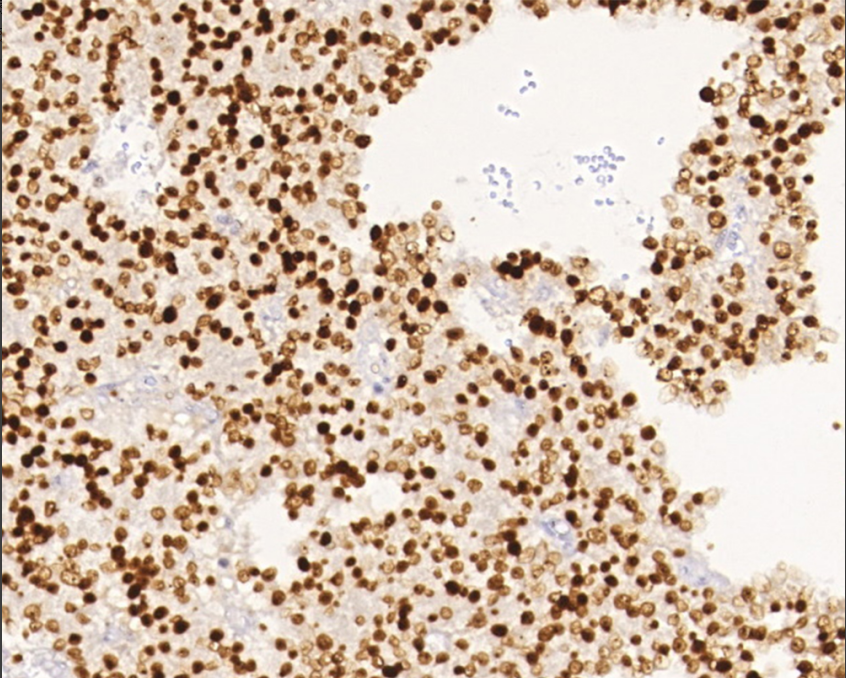

Cellular localization: nucleus

Applicable tissues: paraffin sections

PIT-1, also known as growth hormone factor-1 (GHF-1), is a member of the POU family of homologous structural domains and is essential for the normal development of the anterior pituitary gland.PIT-1 is involved in the differentiation of GH cells, PRL cells, and TSH cells.The expression of PIT-1 is markedly increased in PRL and GH tumors, and is rarely expressed in ACTH and non-functioning adenomas, thus PIT-1 has a role in the cell-specific differentiation and proliferation of human pituitary adenomas, especially GH and PRL adenomas. -1 has a role in cell-specific differentiation and proliferation of human pituitary adenomas, especially GH and PRL adenomas. Polyhormonal adenomas with PIT-1 expression are defined as polyhormonal PIT-1-positive adenomas in the New Pituitary Classification. It is mainly used in the study of pituitary tumors.

PIT-1 antibody reagents can specifically bind to PIT-1 molecular antigens. Immunohistochemistry kits containing PIT-1 antibody reagents are suitable for the classification of pituitary tumors.